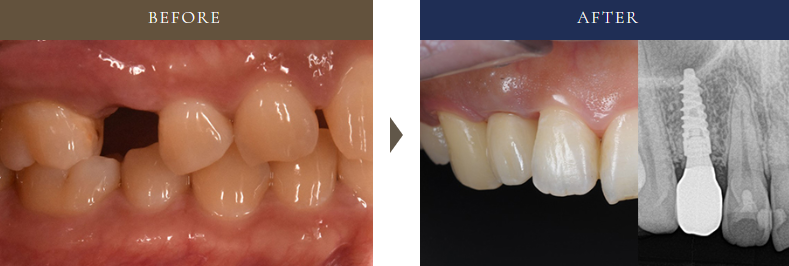

50代女性の左上奥歯に1本インプラントを行った症例。治療前後の口腔内写真とレントゲン比較で効果を確認。

• 治療内容:むし歯で抜歯が必要になった左上の奥歯に、周囲の歯を削らずに1本インプラント治療を実施。

• 治療期間:約5ヶ月

• 費用:310,000円(税込341,000円)

• 補足:CT診断と治療用ガイドを活用し、安全性に配慮。しっかり噛める奥歯としての機能回復を重視しました。